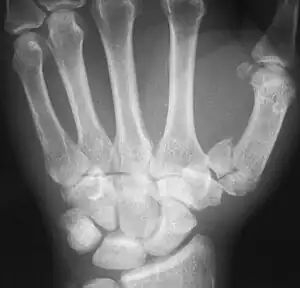

The first metacarpal bone or the metacarpal bone of the thumb is the first bone proximal to the thumb. It is connected to the trapezium of the carpus at the first carpometacarpal joint and to the proximal thumb phalanx at the first metacarpophalangeal joint.

Characteristics

The first metacarpal bone is short and thick with a shaft thicker and broader than those of the other metacarpal bones. Its narrow shaft connects its widened base and rounded head; the former consisting of a thick cortical bone surrounding the open medullary canal; the latter two consisting of cancellous bone surrounded by a thin cortical shell. [1]

The head is less rounded and less spherical than those of the other metacarpals, making it better suited for a hinge-like articulation.

The distal articular surface is quadrilateral, wide, and flat; thicker and broader transversely and extends much further palmarly than dorsally. On the palmar aspect of the articular surface there is a pair of eminences or tubercles which articulate with the radial and ulnar sesamoid bones of the thumb metacarpophalangeal joint; the lateral eminence is larger than the medial.